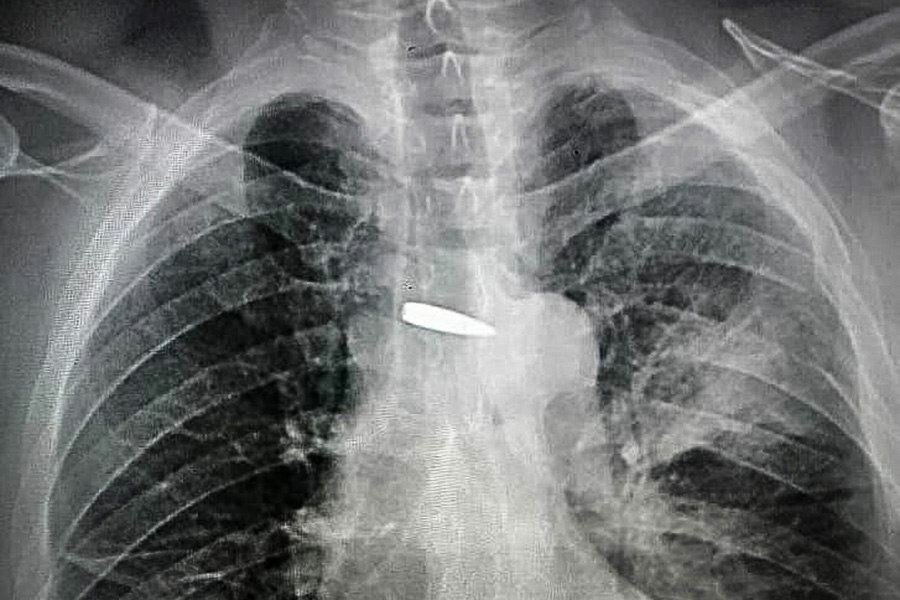

An X-ray of the bullet near his heart went around the world. The bullet passed through the left shoulder, the left lung literally millimeters from the heart and crushed the transverse process of the fifth thoracic vertebra. The former miner of Donbas has recovered and is fighting for Ukraine. Vitaly even left the operating room on his own two feet.